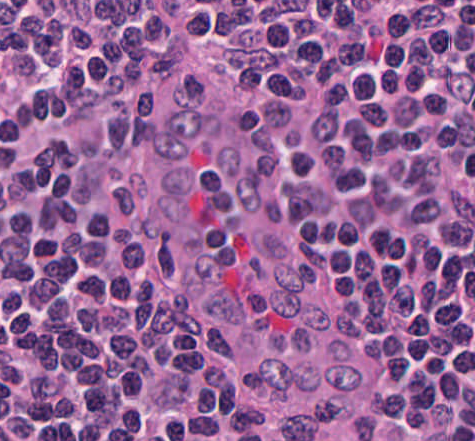

What is this structure?

What is the distinguishing feature of this structure?

Macrophage, the distinguishing feature is the debris found around the cell.